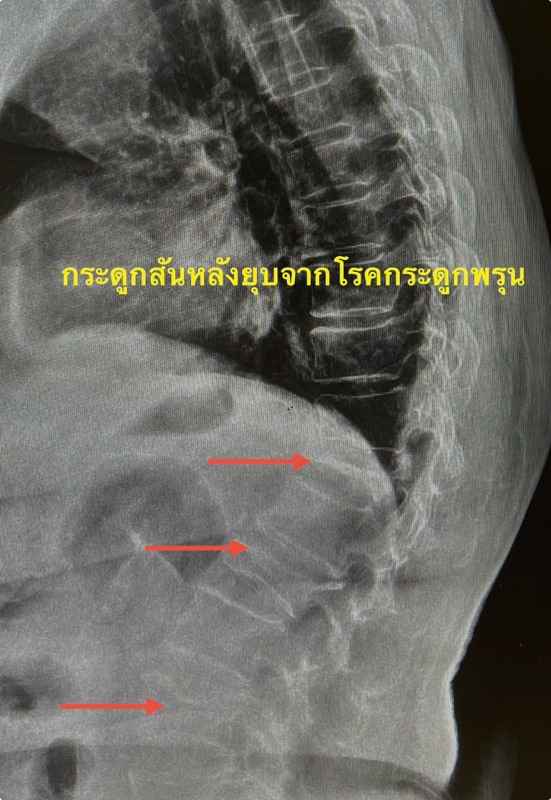

ปวดหลังมาก กระดูกสันหลังยุบหลายตำแหน่งจากโรคกระดูกพรุน — รักษาอย่างไร และป้องกันไม่ให้ยุบซ้ำ

เอกซเรย์พบว่า กระดูกสันหลังยุบ 3 ตำแหน่ง ซึ่งสัมพันธ์กับอาการเจ็บแบบเฉียบพลันของเธอ เมื่อซักประวัติเพิ่มเติมจึงพบว่าเธอน่าจะเป็น “กระดูกพรุนระดับรุนแรง” โดยไม่เคยตรวจมาก่อน

1) เอกซเรย์กระดูกสันหลัง (X-ray)

เป็นการตรวจพื้นฐานที่สุด เห็นตำแหน่งที่ยุบและระดับความรุนแรงได้ดี